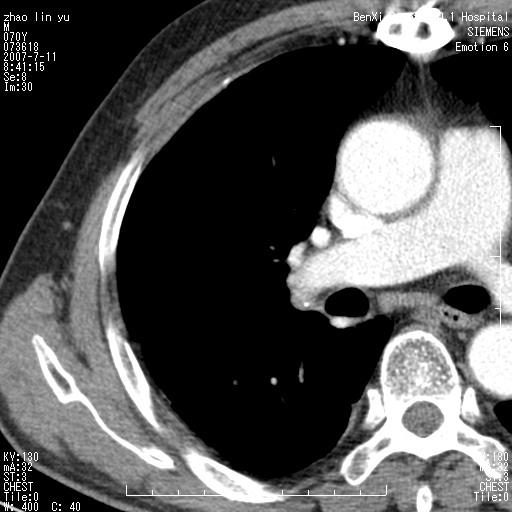

以下是引用王靖旗在2007-7-10 17:12:00的发言:[br] 男、70、咳嗽两个月,半年前换瓣手术,胸片未见异常,于昨天行x片发现右肺上野大片影,行ct扫描,这里是减薄图像,余肺正常。明天晚上会有增强扫描片,到时我会上传。[br][br] 冠状位请大家细看,应该是有意义的,[br][br] 请大家先看平扫发表意见。[br][br]

[br]冠状面[br]

以下是引用zhangzhongshou在2007-7-10 21:43:00的发言:[br]右肺上叶周围型肺癌,以孤立型细支气管肺泡癌可能性大。